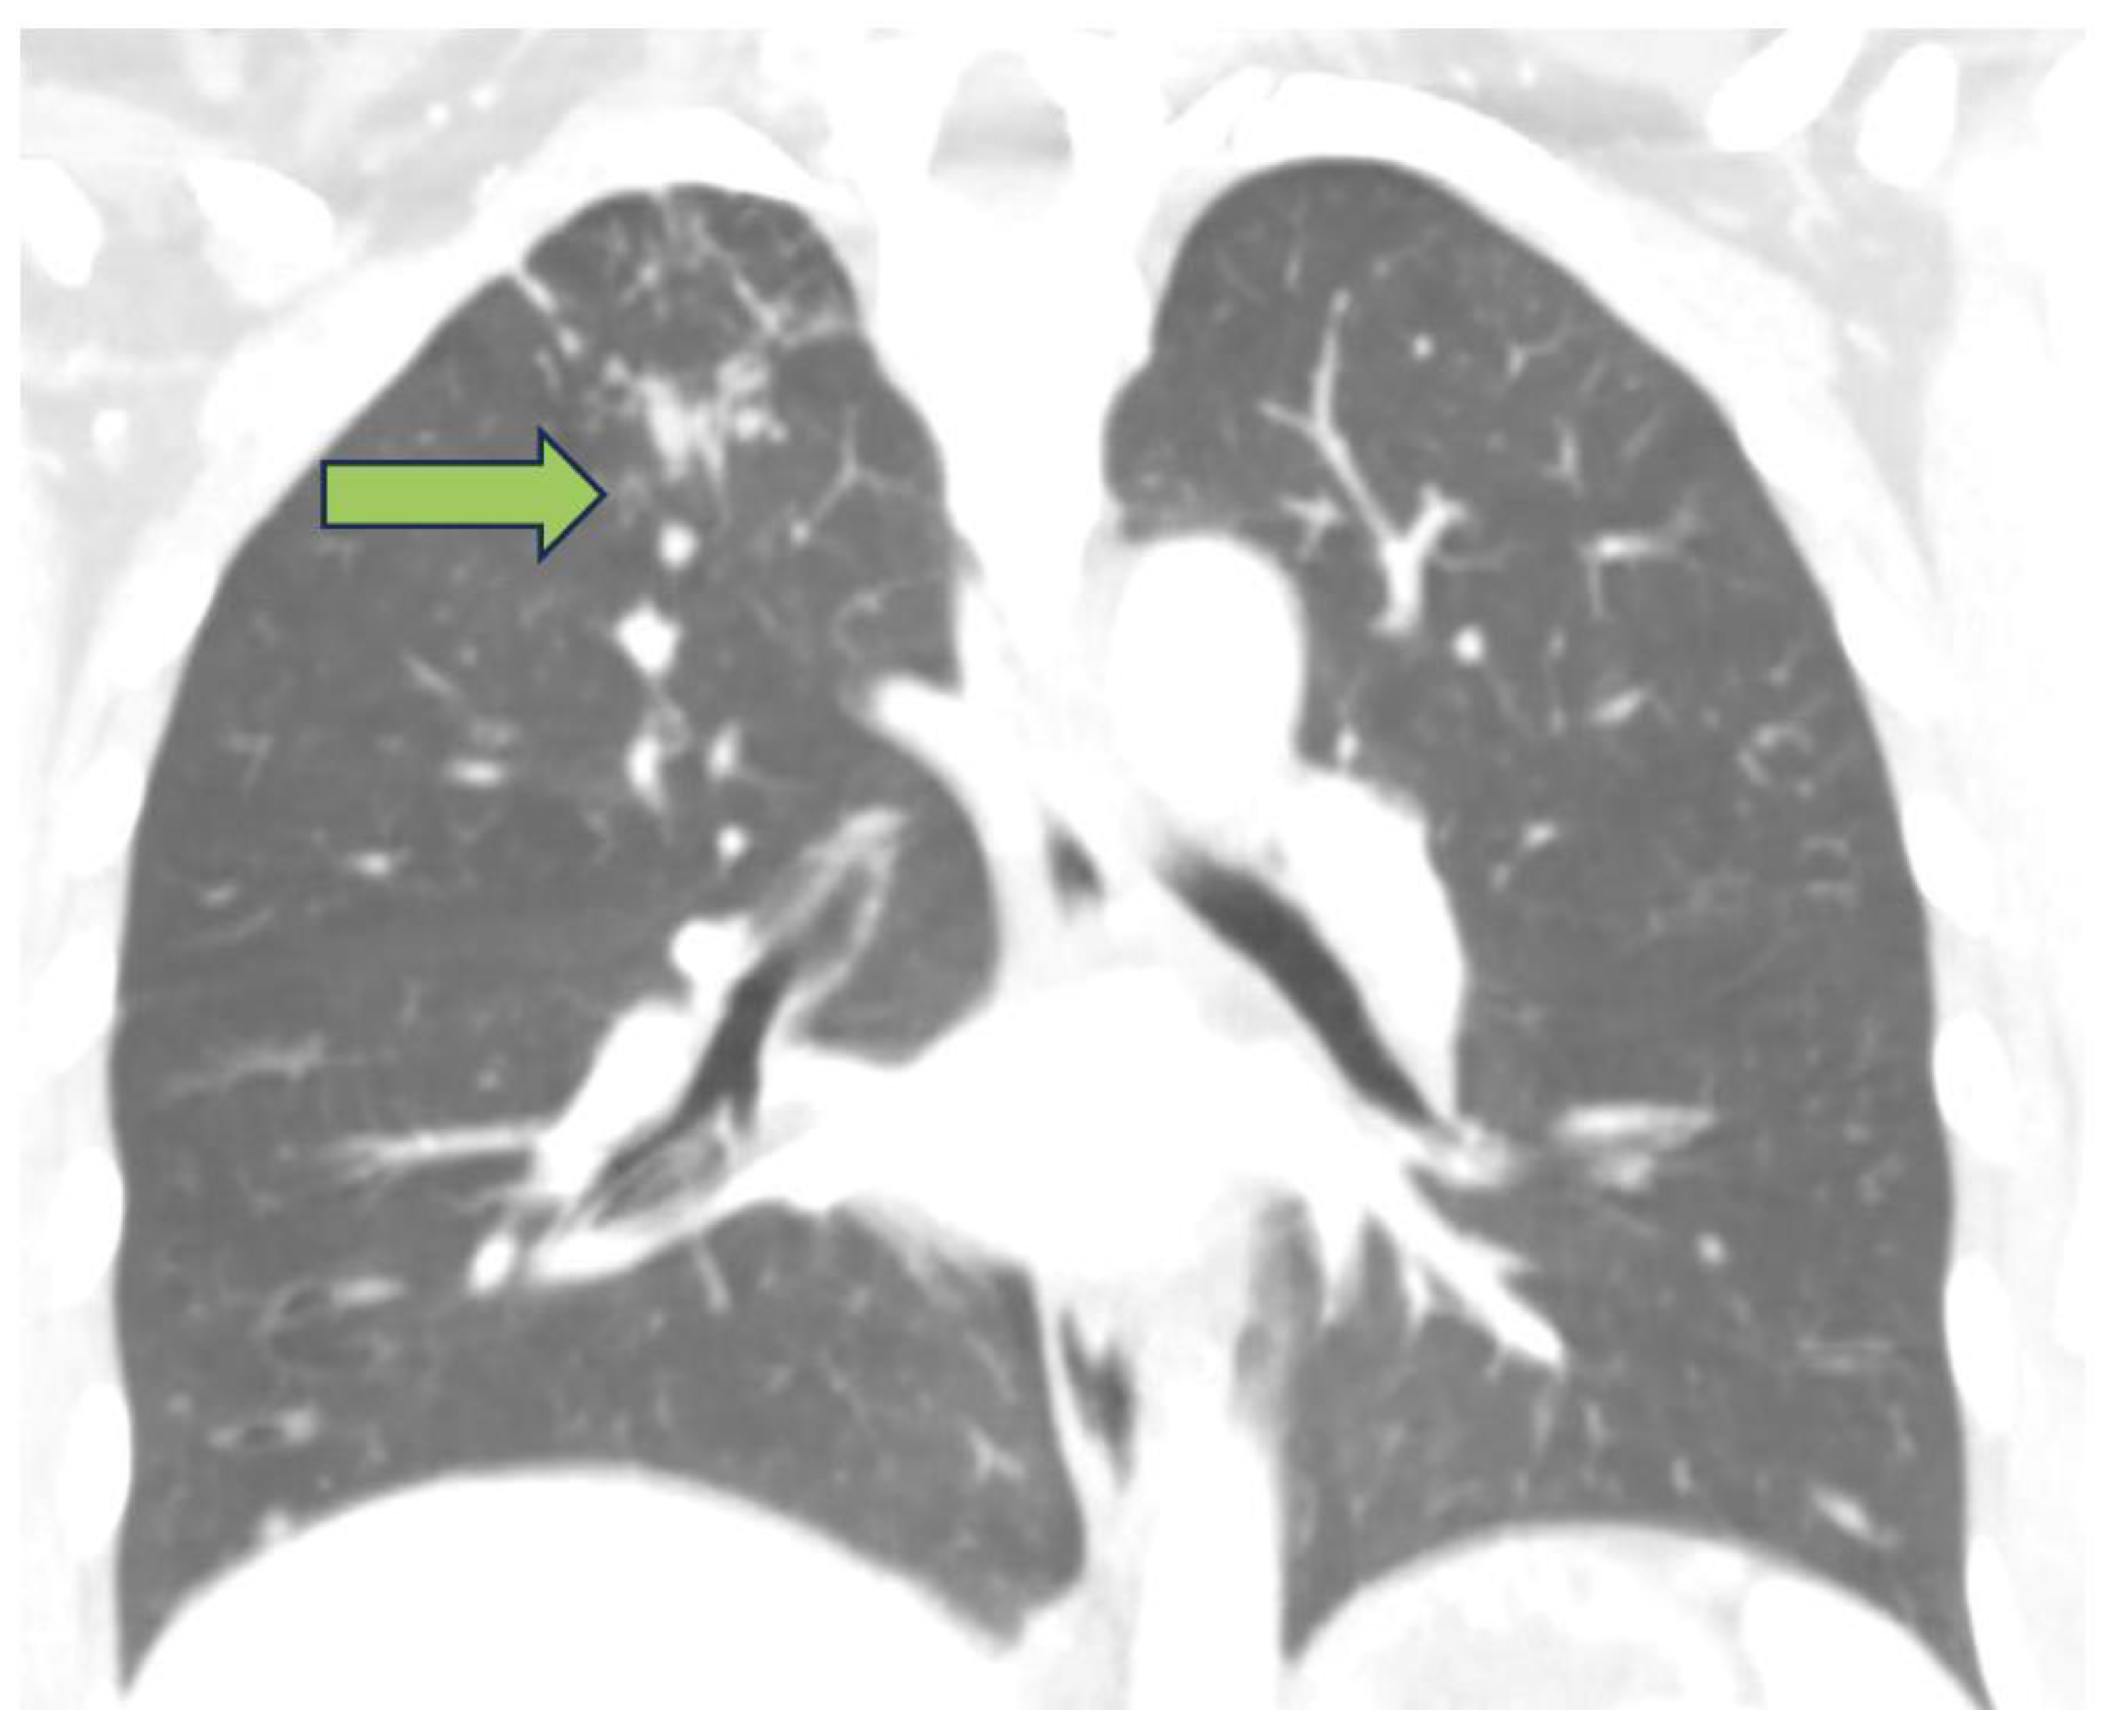

2. Detailed Case Presentation